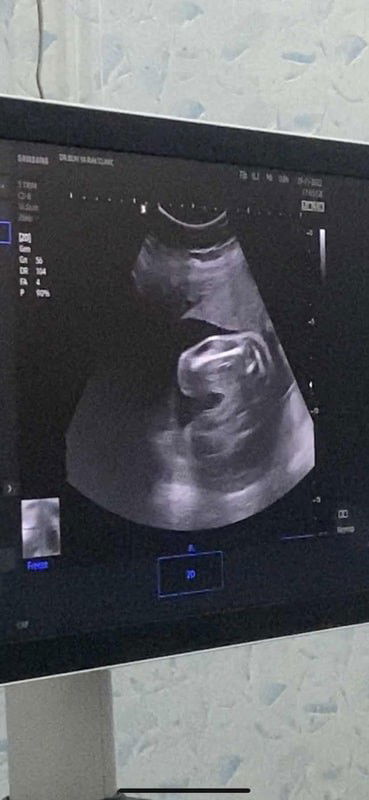

แบบนี้ ผู้หญิงกี่%คะ แม่ๆช่วยดูหน่อยคะ ซาวด์ตอน22w หมอบอกผู้หญิง ซาวด์อีกที26wหมอบอกค่อนไปทางผู้หญิง แม่เลยแอบกลัวว่าจะมีจู๋โผล่ 555+คุณพ่ออยากได้ลูกสาวมาก#ทีมมีนาคม66